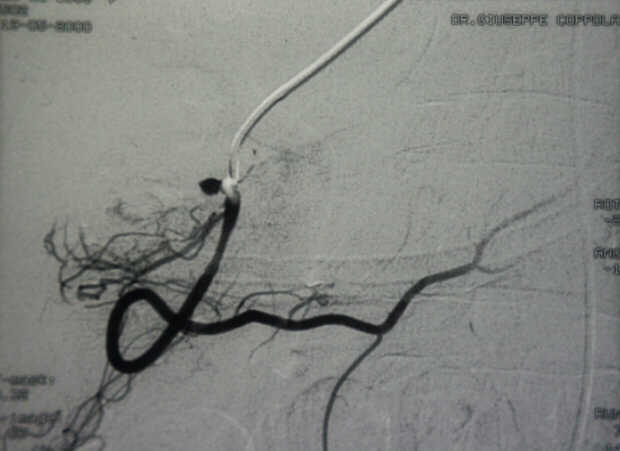

Pancreatic Head Mass: What Can Be Done?

Diagnosis: Angiography

Giuseppe Morelli Coppola, Raffaella Niola, Franco Maglione

Unità Operativa di Radiologia Vascolare ed Interventistica, Azienda Ospedaliera "A. Cardarelli". Napoli, Italy